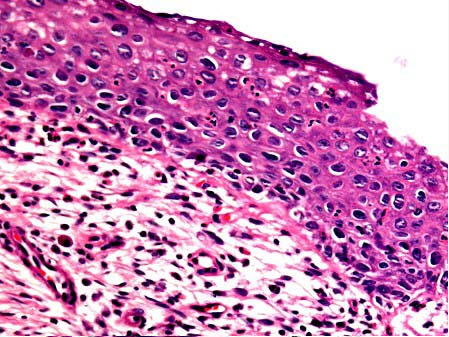

女性,34岁,接触性出血一年余加重一周,行子宫切除,显微镜下见鳞状上皮细胞具异型性,异型细胞超过上皮全层2/3,但不及3/3。如图,应诊断为()

A . CINⅠ级

B . CINⅡ级

C . CINⅢ级

D . 原位癌

E . 浸润癌